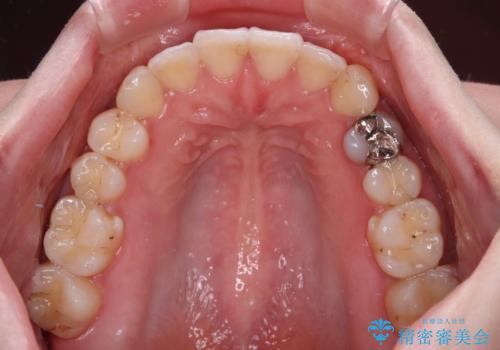

開咬と前方に飛び出した前歯 インビザラインによる矯正治療

- 上下前歯の非接触と叢生を気にして来院された患者様です。

開咬の改善はインビザラインの最も得意とするところであるため、インビザラインを用いて矯正治療を行うこととしました。

舌の突出癖改善のトレーニングをしっかりと行っていただき、上下前歯が接触する咬み合わせを達成することができました。